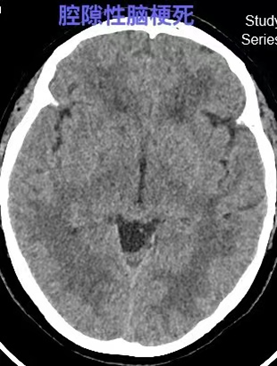

(6)腔隙性脑梗死:是脑梗死的一种,系穿支小动脉闭塞引起的深部脑组织较小面积的缺血性坏死,直径约5~15mm,主要原因是高血压和脑动脉粥样硬化,好发部位为基底节区和丘脑区,中老年人常见。